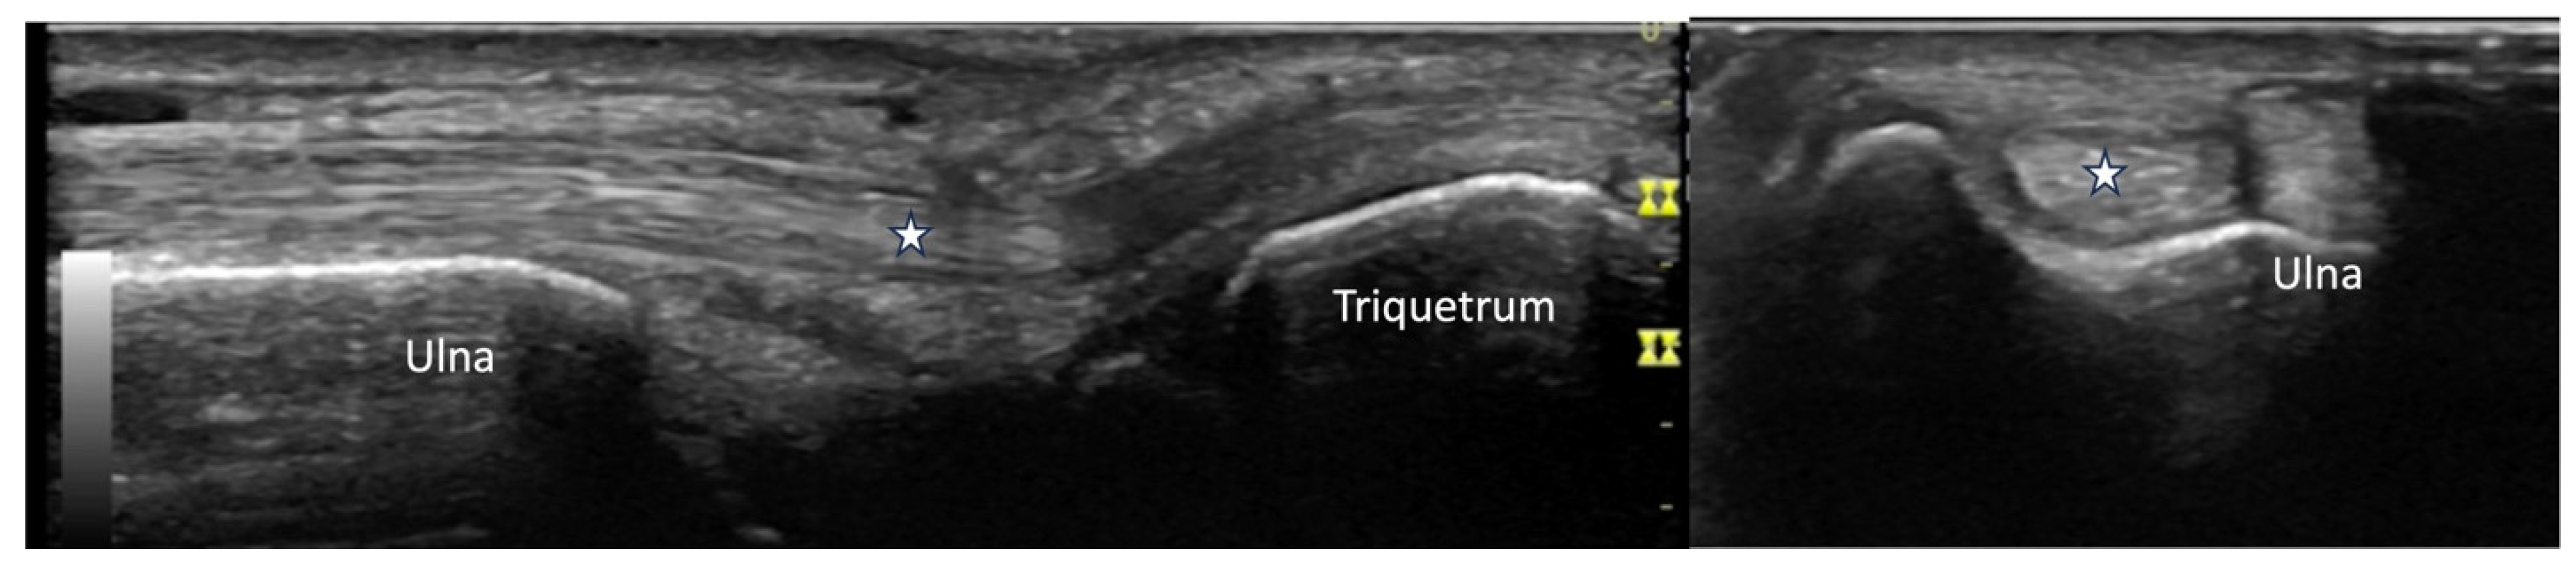

2.4. Vascular Pathology

4.2.3. Ulnar Aspect